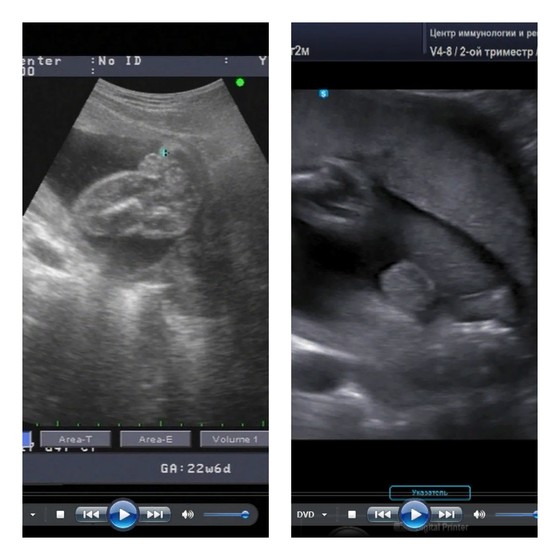

У моих вот так. Скрины с видео УЗИ. Надеюсь, понятно, кто где))

Слева - дочь, справа - сын (Письки в кадре нет - кадр немного другой, хотя тоже с попы, но то, что видите, - это мошонка. Она круглая, цельная, без "разреза", а у девочки как бы "кофейное зерно").